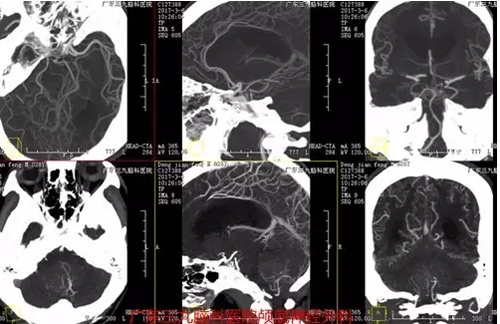

图3:术前CTA提示肿瘤血供